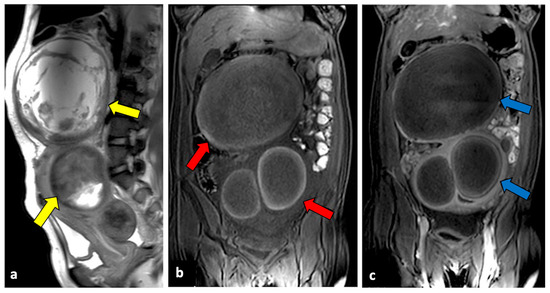

The Diagnostic Accuracy of Magnetic Resonance Imaging for Maternal Acute Adnexal Torsion during Pregnancy: Single-Institution Clinical Performance Review

by Jong Hwa Lee, Hyun Jin Roh, Jun Woo Ahn, Jeong Sook Kim, Jin Young Choi, Soo-Jeong Lee and Sang Hun Lee

Background: For acute adnexal torsion of pregnant women, appropriate treatment based on an accurate diagnosis is especially important for fertility preservation and timely treatment. The 2017 American College of Obstetricians and Gynecologists (ACOG) Committee Opinion No. 723 announced its practice-changing guidelines to ensure [...] Read more.

Background: For acute adnexal torsion of pregnant women, appropriate treatment based on an accurate diagnosis is especially important for fertility preservation and timely treatment. The 2017 American College of Obstetricians and Gynecologists (ACOG) Committee Opinion No. 723 announced its practice-changing guidelines to ensure that diagnostic magnetic resonance imaging (MRI) conducted during the first trimester and gadolinium exposure at any time during pregnancy are safe for fetal stability. Unfortunately, few studies have been performed to evaluate the usefulness of the diagnostic accuracy of MRI for acute adnexal torsion during pregnancy. Objective: We sought to determine the efficacy of diagnostic MRI modality using multiparameter for maternal adnexal torsion during pregnancy. Methods: From 1 January 2007 to 31 January 2019, 131 pregnant with MRI tests were reviewed. In this retrospective cohort study, 94 women were excluded due to conditions other than an adnexal mass, and 37 were identified through MRI analyses conducted before surgery for suspected adnexal torsion. The primary outcome was the diagnostic accuracy of sonography and MRI, and the secondary outcome was the usefulness of Apparent diffusion coefficient (ADC) values for predicting the severity of hemorrhagic infarction between the medulla and cortex of the torsed ovarian parenchyma. Results: Our study demonstrates that in the diagnosis of adnexal torsion during pregnancy, the sensitivity, specificity, positive predictive value, and negative predictive value are 62.5%, 83.3%, 90.9%, and 45.5% for sonography and 100%, 77.8%, 90.5%, and 100% for MRI. MRI results in surgical-proven adnexal torsion patients revealed unilocular ovarian cysts (36.8% (7/19)), multilocular ovarian cysts (31.6% (6/19)), and near normal-appearing ovaries (31.6% (6/19)). Pathology in adnexal torsion revealed a corpus luteal ovarian cyst (63.2% (12/19)) and underlying adnexal pathology (46.8% (7/19)). Maternal adnexal torsion during pregnancy was more likely to occur in corpus luteal ovarian cysts than in underlying adnexal masses (odds ratio, 2.14; 95% confidence interval (CI), 0.428–10.738). MRI features for adnexal torsion were as follows: tubal wall thickness, 100% (19/19); ovarian stromal (medullary) edema, 100% (19/19); symmetrical or asymmetrical ovarian cystic wall, 100%(19/19); prominent follicles in the ovarian parenchyma periphery, 57.9% (11/19); periadenxal fat stranding, 84.2% (16/19); uterine deviation to the twisted side, 21.1% (4/19); and peritoneal fluid, 42.1% (8/19). The signal intensity of the ADC values of the ovarian medulla and cortex were compared between the cystectomy and detorsion (CD) and salpingo-oophorectomy (SO) groups. The ADC values of the CD and SO groups were 1.81 ± 0.09 × 10−3 mm2/s and 1.91 ± 0.18 × 10−3 mm2/s, respectively (P = 0.209), in the ovarian medulla and 1.37 ± 0.32 × 10−3 mm2/s and 0.96 ± 0.36 × 10−3 mm2/s, respectively (P = 0.022), in the ovarian cortex. The optimal cut-off value of ADC values for predictable total necrosis in the torsed ovarian cortex was ≤ 1.31 × 10−3 mm2/s (area under the curve (AUC) = 0.81; 95% CI 0.611–1.0; P = 0.028). Conclusion: Our data showed that maternal adnexal torsion during pregnancy occurred in most corpus luteal cystic ovary cases and some normal-appearing ovary during the 1st and 2nd trimesters of gestation. Therefore, this study is the first study to elaborate on the existence or usefulness of the diagnostic MRI for acute maternal adnexal torsion during pregnancy and to provide a predictive diagnosis of the severity of hemorrhagic infarction for deciding surgical radicality. Full article